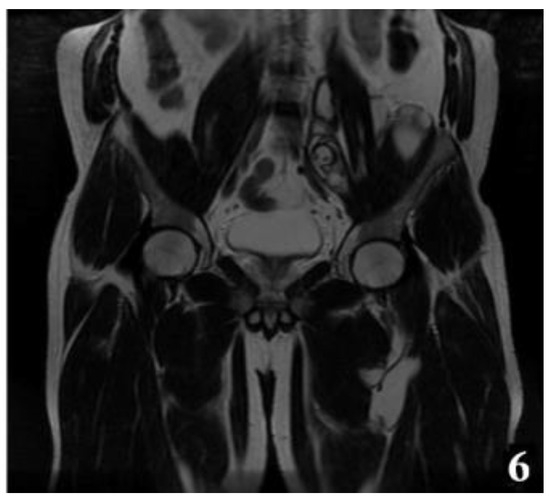

Figure 6.

T2W MRI sequences, coronal—Hydatid cyst of left iliopsoas muscle and left thigh, with daughter cells and Serpent sign present [8] (part 2).

The MRI examination was performed on two patients for surgical purposes, to establish the relationship with other organs or vital structures and to guide the indication and the surgical plan. It is important to note the case of a 32-year-old male patient, hospitalized for the presence of a tumor formation at the base of the left thigh, in which the native and contrast enhanced MRI examination of the pelvis and thigh revealed: urinary bladder without parietal thickenings or endoluminal pathological processes; seminal vesicles without pathological signal changes; prostate measuring 4.7/3.2 cm, homogeneous, without pathological contrast plugs; without suspicious adenomegaly at the pelvic level; replacement process of polylobate space, which is relatively well demarcated, predominantly with fluid signal, multiple septate, without diffusion restriction, with gadophilia present at the peripheral and intralesional septal level, starting from the vicinity of the psoas and iliac muscle on the left side and extending into caudal direction through the anterior portion of the inguinofemoral region on the left side to the proximal region of the left thigh, and coming into contact with the common iliac, external iliac and femoral vessels on the left side (apparently with preserved flow at their level and with the apparently left femoral diaphysis but no macroscopic invasion phenomena at this level); previously described space-replacing process, which extends over a cranio-caudal distance of approximately 33 cm and shows inhomogeneous signal at the level of some of the intralesional cystic areas; deep to the gluteus maximus muscle on the left side, a relatively well-defined area can be seen, with a polylobate contour, multiple septa, with a similar appearance to the previously described space-replacing process, with dimensions of 2.9/2.75 cm—possibly parasitic cystic lesions (Figure 4, Figure 5, Figure 6, Figure 7, Figure 8 and Figure 9).